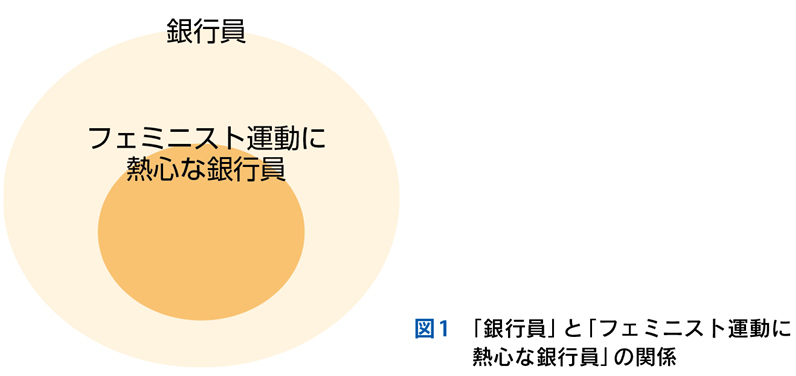

▶ 分析的診断推論とは,論理的に選び出した,可能性のある複数の診断を検討することである。膨大な数の疾患の中から可能性のある診断群を選び出すためには,まず疾患全体を含む空間の中に,「この内側に確実に真の診断がある(この外側には確実に真の診断はない)」という「枠」を置くことが必要である。仮にそうせずに推論を進めるのであれば,広大な空間内から行き当たりばったりで疾患を選んでいくことになる。これは要するに直観的診断の繰り返しであり,システム1が磨かれていなければ当たるも八卦,当たらぬも八卦で診断にたどり着けるかどうかわからない。

▶ 疾患全体という空間内に診断の可能性を限定する「枠」(フレーム)を置くことは,分析的診断の必要条件となる重要な一歩である(図2)。これを筆者は「フレーミング」と呼ぶ。

▶ 症例によっては,ここまで述べたような条件を満たす問題を複数定義できることがある。この場合は,それぞれの問題が描くフレームが重なり合うところに診断があると考えるとよい(図3)。